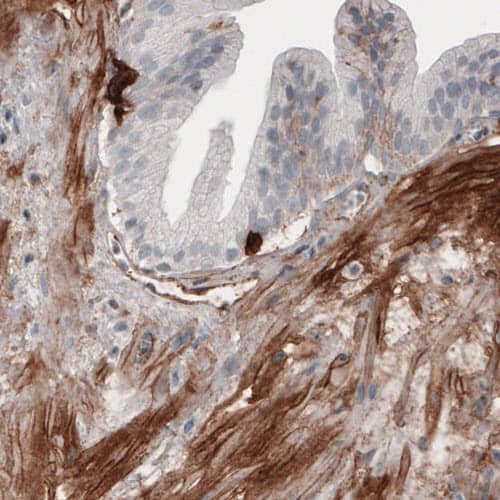

Staining of human small intestine shows strong immunoreactivity in the connective tissue.